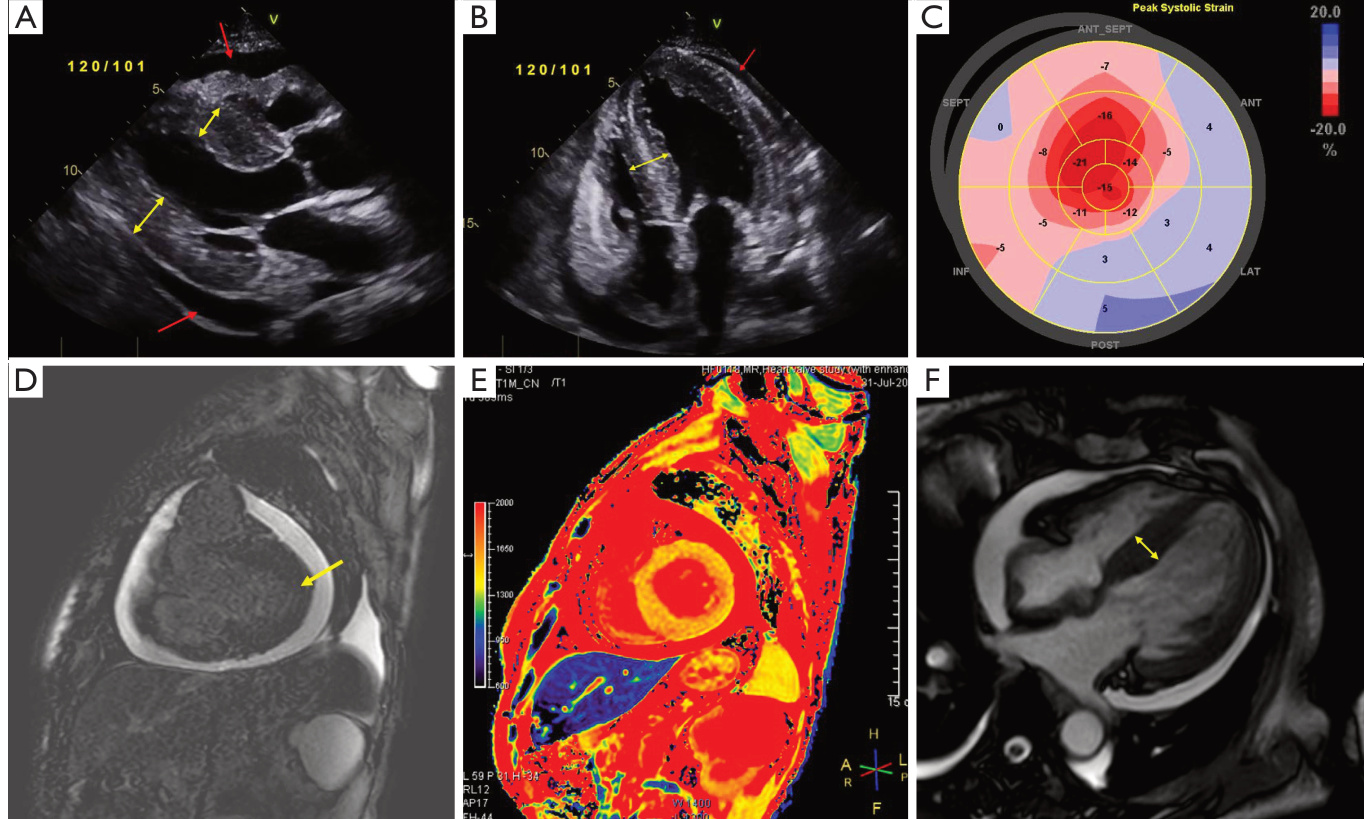

病史摘要:33 岁女性,无吸烟饮酒及特殊家族史,因“活动后胸闷、气短”于 2020 年 9 月 4 日就诊。胸部高分辨率 CT 提示左下叶基段肿块阴影伴左肺散在小结节。心包积液和胸腔积液涂片、支气管镜病理均证实为左下叶基底段腺癌,基因检测示 EGFR 外显子 19 突变和 TP53 突变,临床诊断左肺腺癌(T3N3M1a IVA 期,EGFR ex19del+,TP53+)。 诊疗过程:一